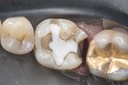

Kyle Chock #14 pre-op

Kyle Chock #14 caries removal

Kyle Chock #14 prep

Kyle Chock #14 prep with pin

Kyle Chock #14 impression

Kyle Chock #14 model

Kyle Chock #14 castings

Kyle Chock #14 castings on model

Kyle Chock #14 finish